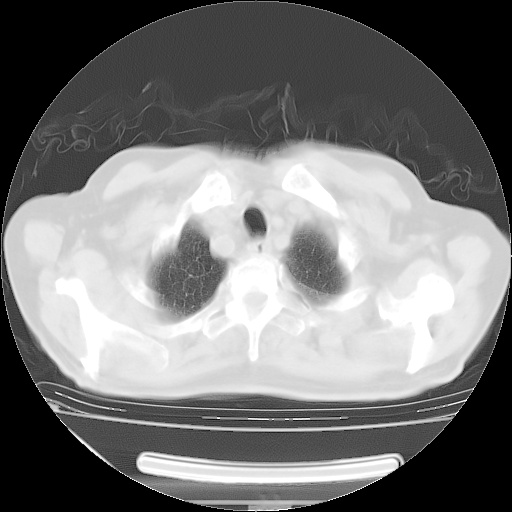

今天复查肺部CT,发现双肺广泛磨玻璃样改变。所以我把3月19日和5月9日相隔50天的肺部CT上传。请大家会诊。

2009年3月19日肺部CT片。

2009年3月19日肺部CT